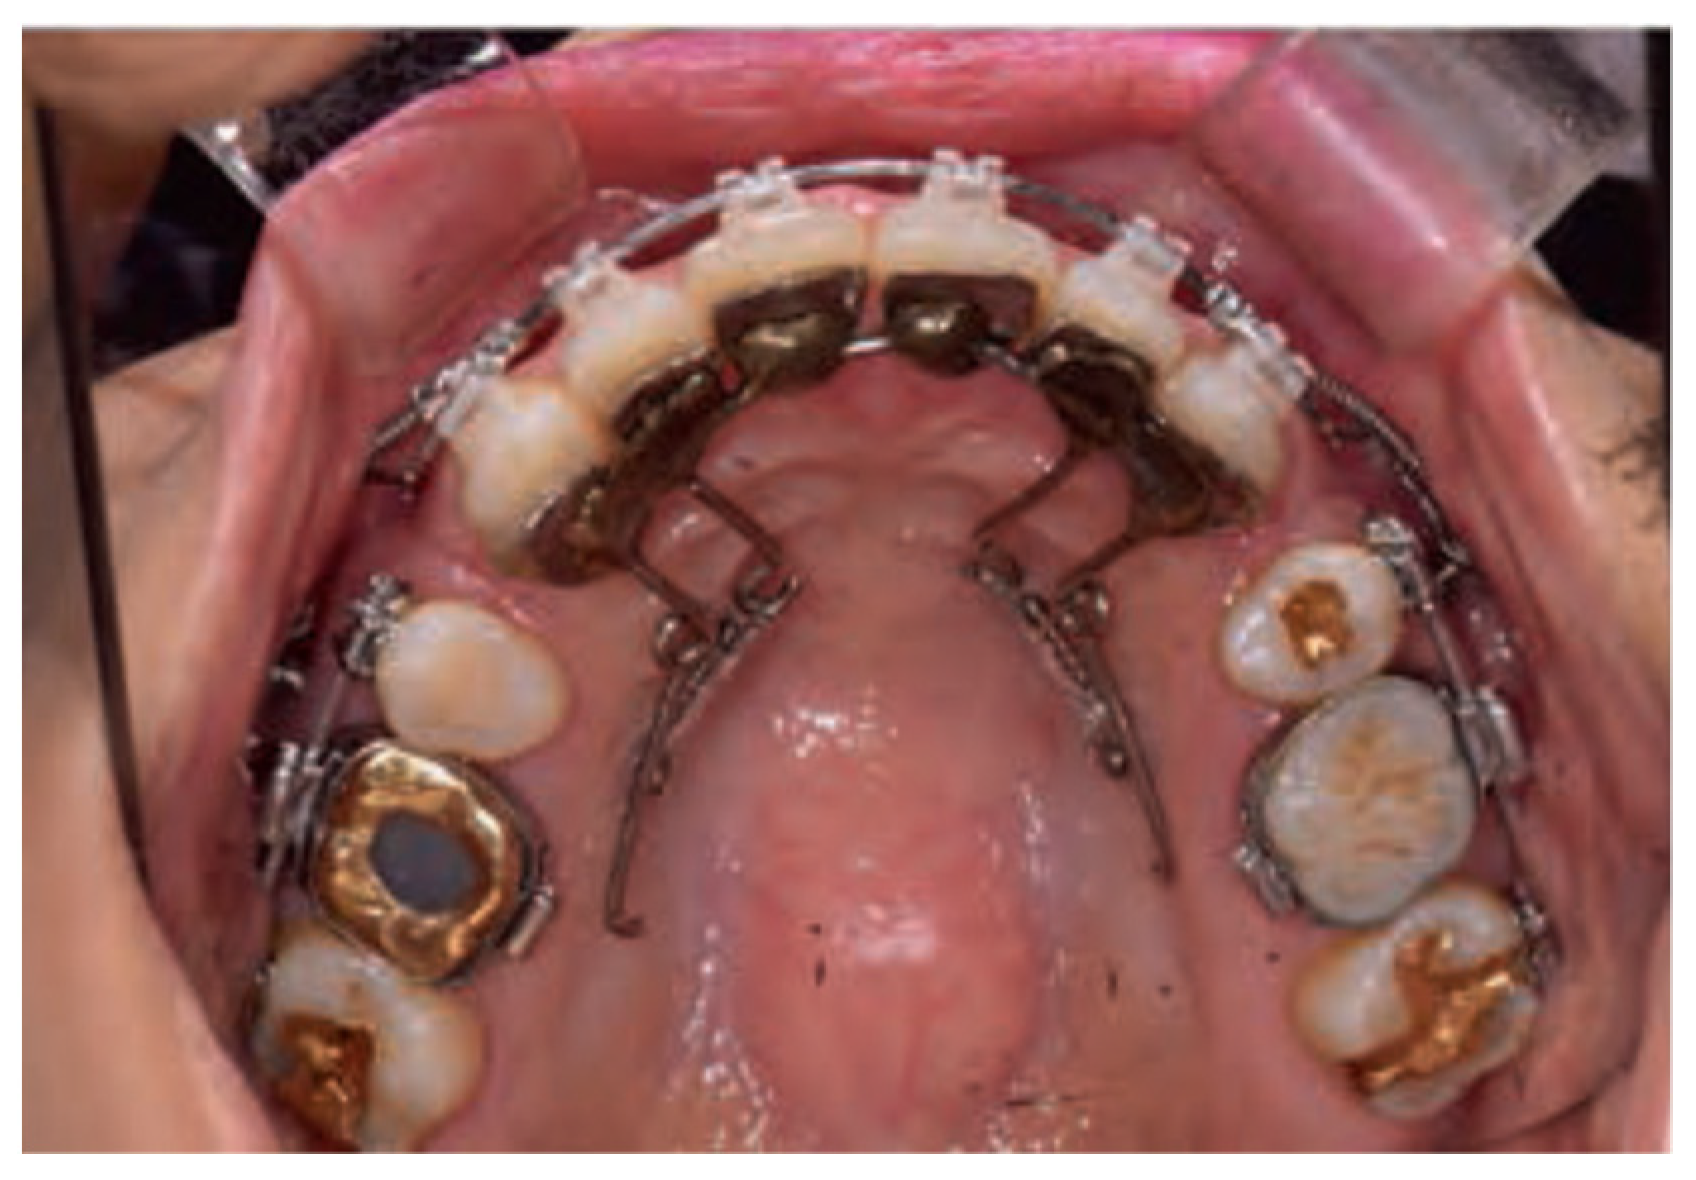

The APLR basically consists of a C-lingual retractor bonded to the lingual surfaces of the six anterior teeth, lever arms, posterior splints, and posterior tubes, which act as pathways for the guide bar. The lever arms are soldered to the anterior splint, and the posterior tubes are soldered to the posterior splint. A guide bar with a diameter of 0.036-in extending from the lever arm passes and slides through the posterior tube (Figure 7) [1,5]. Friction in the APLR is minimized compared to conventional lingual brackets as the friction in the APLR occurs only between the guide bar and the posterior tube during retraction.

Figure 7.

Antero-posterior Lingual Retractor (APLR) appliance.

- (1)

- Anterior Segment

The anterior part of the APLR was similar to that of the CLR. In addition, the 0.036-in stainless steel guide bar, soldered to the lever arm or attachment pad extends posteriorly into the posterior tube [1,5].

- (2)

- Posterior Segments

The posterior connecting wire is soldered to the posterior attachment pad to be positioned on the second premolar, first and second molar to form a posterior splint. A posterior tube 1 mm in diameter, typically parallel to the occlusal plane is soldered to the first molar area of the posterior splint and acts as a sliding path. The guide bar soldered to the anterior segment passes through the posterior tube and the clearance between the guide bar and posterior tube is approximately 0.1 mm [1,5].

- (3)

- Accessory Parts

The transverse dimension is controlled by adding a TPA. It is soldered to the extended arm which is connected to the first molar pad. In some cases, additional hooks are added to the TPA for posterior intrusion or torque control [1].

- (4)

- TSADs

Generally, miniscrews or C-palatal plate are placed in the midpalatal area for torque and vertical control of anterior teeth [5].